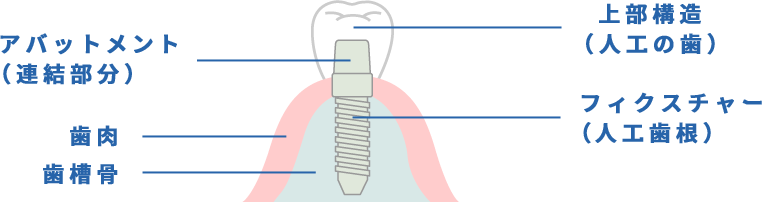

まるで自分の歯のような噛み心地

歯を失ってしまっても、食事さえできればそれで良いと放置していませんか?

しかしその状態のままで生活を続けると、歯を失った部分から少しずつバランスが崩れ、咬み合う歯が伸びたり、歯列が乱れたりなどの症状を起こすことがあります。

歯を失った際の治療法はいくつかありますが、中でもインプラントは見た目・装着感ともに最も自然で、ご自身の歯のような噛み心地が好評の治療法です。

インプラントは、フィクスチャー(人工歯根)とアバットメント(連結部分)と上部構造(人工の歯)で構成されています。

顎の骨に埋め込むので、ご自身の歯のような感覚です。

インプラント治療は外科手術が必要となるため、事前の診査がとても重要です。 当院では最新のCTとレントゲンを備え、骨の位置はもちろんのこと、神経や血管の位置までしっかりと把握してから手術を行いますので、より安全で安心なインプラント治療を行うことができます。 また、最新の機器を使用することで被曝量も必要最低限に抑えられているため、身体にも負担が少なく安心です。